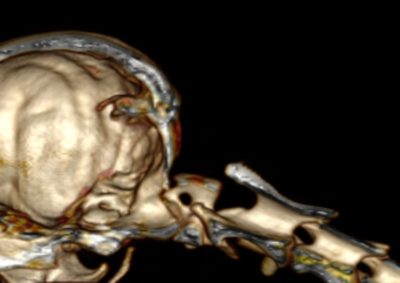

脳神経外科 注意 ボタンをクリックした先に、治療中および手術中の画像が説明で使用されている場合がございます。 そのような画像に弱い方は閲覧なさらないようお願いいたします。 脳神経外科 Ventral Slot 脳神経外科 椎間板ヘルニア 脳神経外科 PLDD 多発性頸部椎間板ヘルニア 脳神経外科 椎間板ヘルニア 脳神経外科 経皮的レーザー椎間板除圧術 PLDD 脳神経外科 椎間板ヘルニア 脳神経外科 環軸椎不安定症に対する環軸固定術 脳神経外科リハビリテーション… 脊髄梗塞 脳神経外科 ベントラルスロット 脳神経外科 ベントラルスロット 脳神経外科 環軸不安定症 脳神経外科内科 Feline Meningoencephalomyelitis of Unknown Origin : 猫の... <1234567> 症例カテゴリー 放射線治療整形外科軟部組織外科脳神経外科内科腫瘍外科救急・集中治療リハビリテーション科腫瘍内科内視鏡科脳神経科呼吸器外科中医・漢方猫の腎移植循環器科